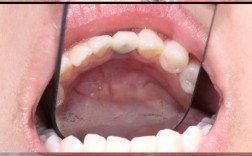

正畸期间,托槽、弓丝等矫治装置会增加牙齿清洁难度,若患者本身存在牙龈炎(表现为牙龈红肿、刷牙出血),菌斑堆积会进一步诱发或加重炎症,长期慢性炎症会导致牙龈纤维破坏,牙槽骨吸收,进而出现牙龈退缩,使牙根暴露,不仅影响美观,还可能增加牙齿敏感和龋坏风险。

即使正畸前牙周健康良好,治疗过程中仍需加强维护,因为牙齿移动本身会对牙周组织产生暂时性影响,且矫治装置增加了清洁难度,维护要点包括:

- 强化口腔卫生:使用正畸专用牙刷(如小头牙刷)、牙缝刷、正畸牙线等工具,彻底清洁托槽周围、弓丝下方及牙龈边缘,每日至少两次,饭后及时漱口。

- 定期牙周复查:正畸期间每3-4个月进行一次牙周检查,包括PD、BI测量,必要时进行洁治,及时发现并处理牙龈炎、牙周炎等问题。